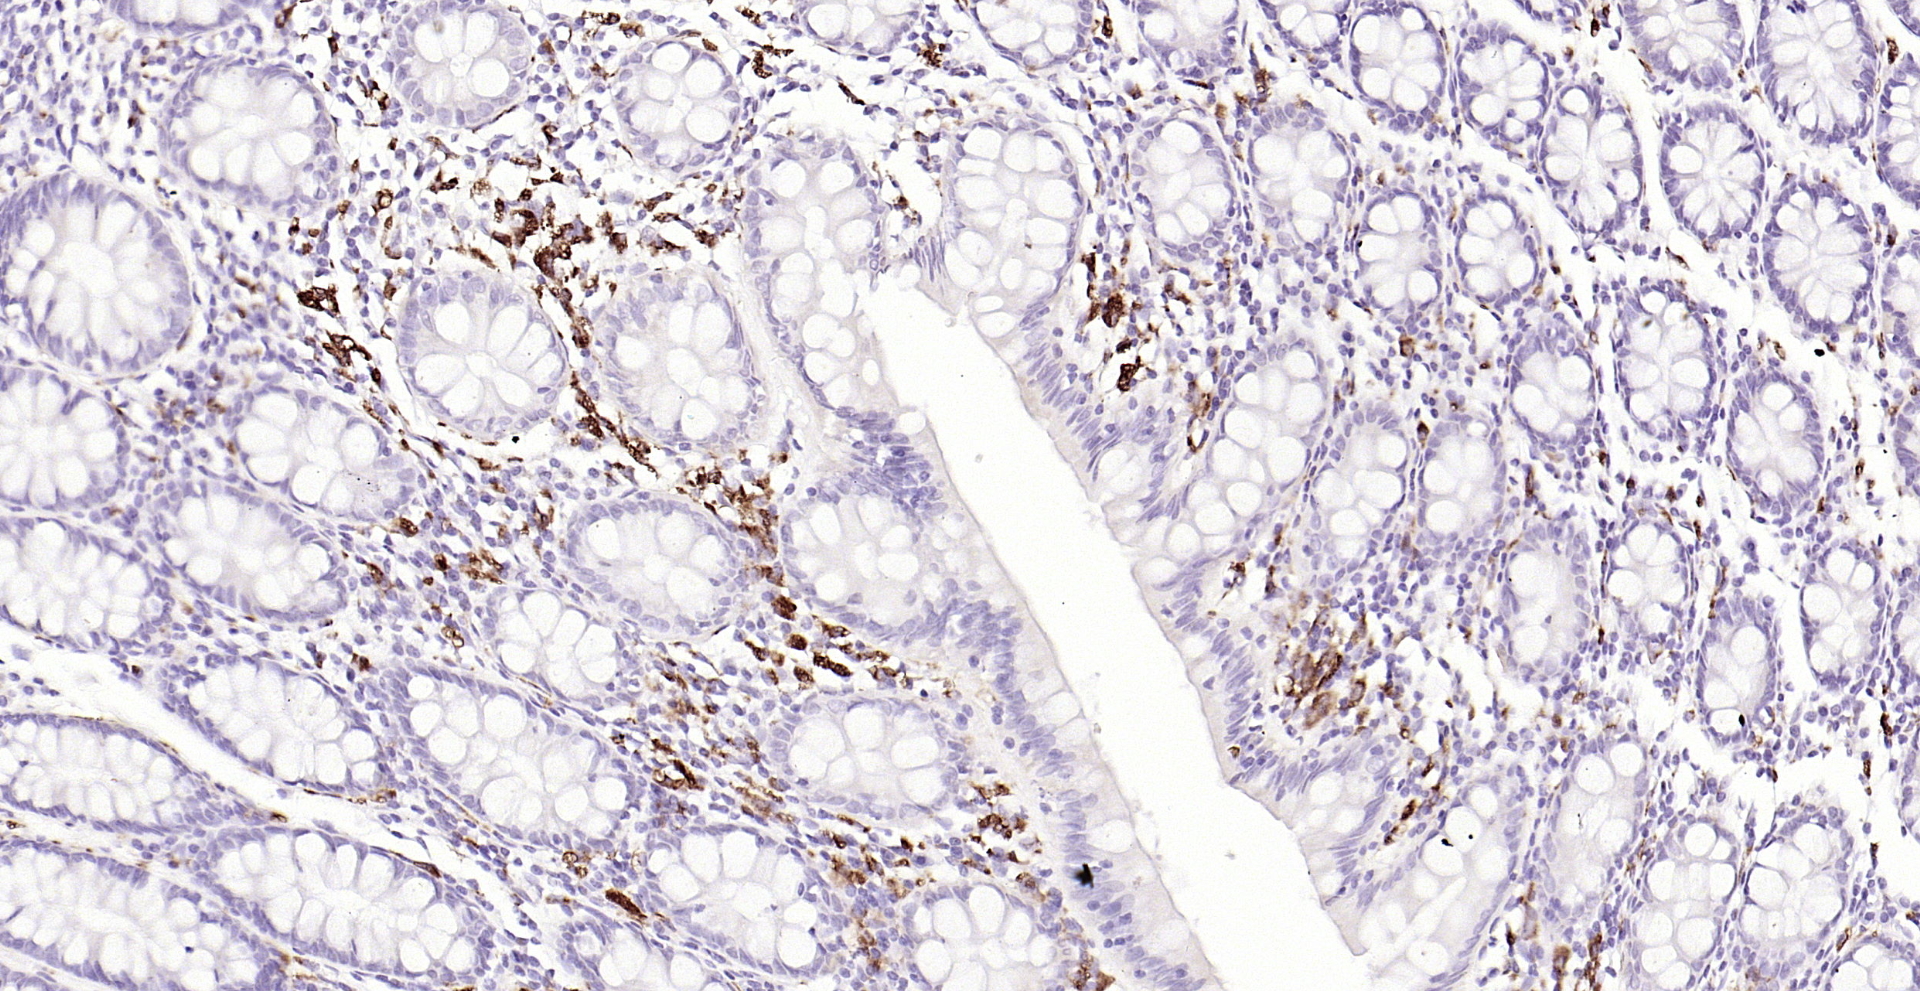

CD68 Polyclonal Antibody

Applications ELISA, IHC-P, IF(IHC-P), IF(IHC-F), IF(ICC)

IHC-P 1:200-400